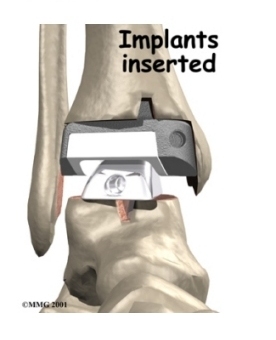

Each artificial ankle prosthesis is made of two parts:

- The tibial component is the part of the artificial joint that replaces the socket portion of the ankle (the top section).

- The talus component replaces the top of the talus.

The tibial component is usually made up of two parts: a flat metal piece called a metal tray that is attached directly to the tibia bone, and a plastic cup that fits onto the metal piece, forming a socket for the artificial ankle joint. The talus component is made of metal and fits into the socket of the tibial component.

Your surgeon may use a special type of epoxy cement to attach the metal components to the bone. This is called a .

Some surgeons prefer to put the new joint in without using cement. This is called an . The surface of this type of prosthesis bears a fine mesh of holes that allow bone to grow into the mesh and attach the prosthesis to the bone.